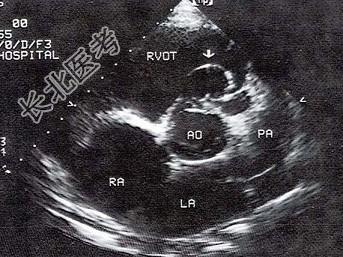

- 单项选择题该病例最可能的诊断为   (   )

A、室间隔缺损

B、主动脉右冠窦瘤破裂

C、右室流出道狭窄

D、主动脉右冠瓣脱垂

E、房间隔膨出瘤